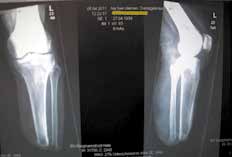

Sehr lange Unterschenkelstümpfe (kurz oberhalb der Spongiosa der distalen Tibia) sind auf die Dauer wegen der Gefahr zunehmender trophischer Störungen über die Jahre auch bei sehr geringem Endkontakt in der Prothese problematisch (Abb. 11). Viele Jahre scheint ein langer US-Stumpf gut versorgbar zu sein, wenn die Amputation im Kindesalter stattfindet und wenn Tibia- und Fibulaende sich fast auf gleicher Höhe befinden und somit eine breitere Auflagefläche für den Endkontakt darstellen (Abb. 12). Gewebe und arterielle Durchblutung stellen sich offenbar im Kindesalter auch besser auf die Gesamtsituation ein. Allgemein gilt aber: Der beste Unterschenkelstumpf ist der, der mit Muskulatur unter physiologischer Vorspannung gedeckt ist.

Im Folgenden werden anhand von Fotos aus dem Archiv des Verfassers einige einschlägige Fälle vorgestellt, um häufig vorkommende Fehler aufzuzeigen (Abb. 1–10).